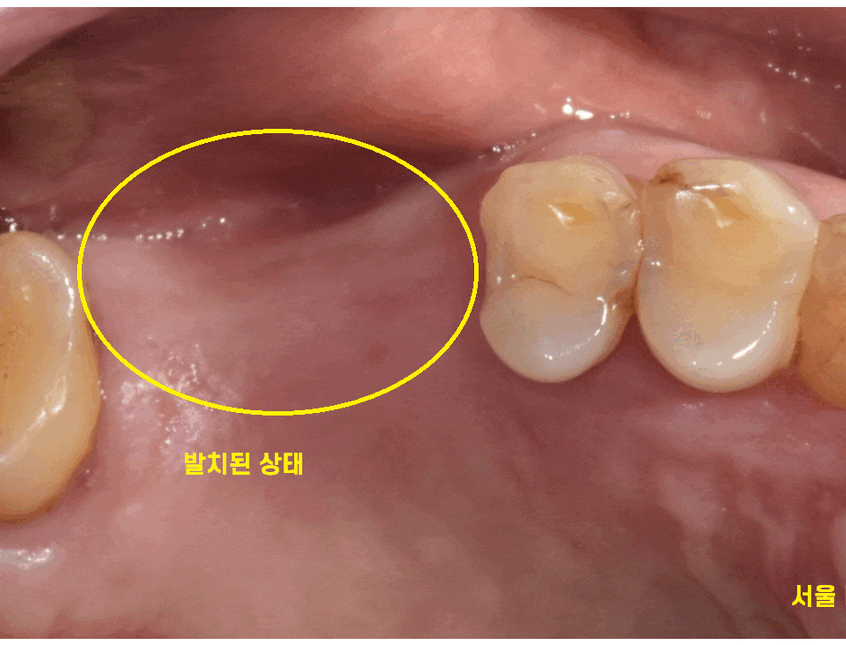

오른쪽 위에 부분은 발치 된지 오래된 상태

치아가 없어서 주로 왼쪽으로 식사를 하다보니

왼쪽이 불편하다고 하셨습니다.